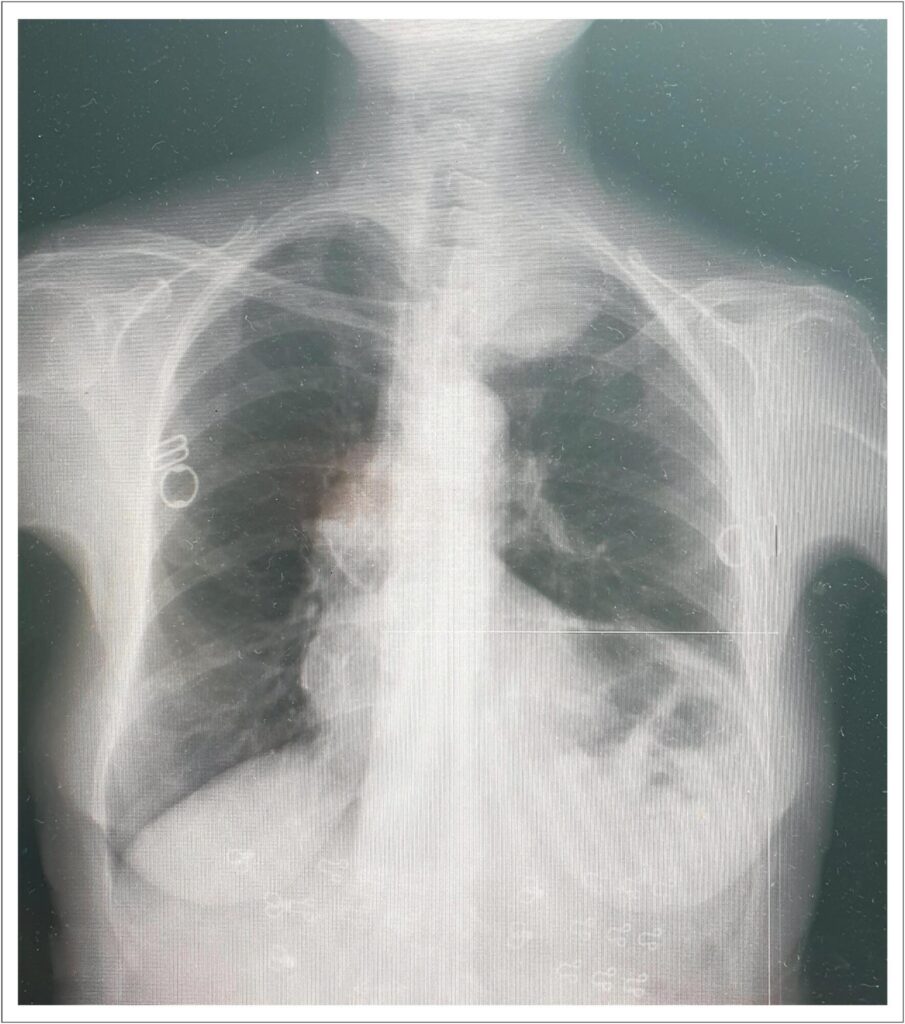

Subclavian artery aneurysms are rare vascular anomalies that carry significant risks, including thromboembolism, ischemia, and rupture. This case report describes a 71-year-old female patient presenting with left arm ischemia, including pain, numbness, and weakness, caused by a left subclavian artery aneurysm complicated by distal thrombosis. Imaging revealed a 65 × 55 mm aneurysm with a 2.5 cm thrombotic occlusion. The aneurysm was treated with an endovascular approach, utilizing a vascular plug deployed via femoral access. This was preceded by failed attempts to access the lesion through the radial approach due to the presence of thrombotic occlusion and complex vascular anatomy. After the procedure, the patient experienced significant symptom relief, and follow-up imaging confirmed thrombosis of the aneurysm sac. This case highlights the effectiveness of endovascular techniques in managing complex subclavian artery aneurysms and emphasizes the importance of individualized treatment strategies and close follow-up.